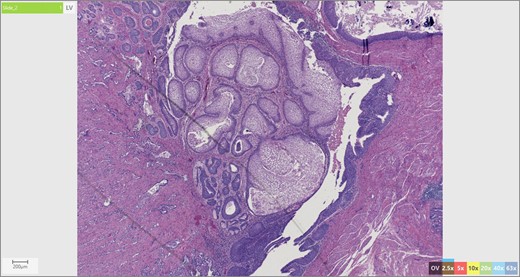

The patient’s surgical pathology was consistent with a low-grade neuroendocrine neoplasm arising within a mature cystic teratoma. The neoplasm took up 25% of the tumor volume and the rest was occupied by elements of a mature cystic teratoma. Histologically, squamous epithelium, sebaceous glands, thyroid, salivary gland, urothelium and gastrointestinal epithelium were all demonstrated (Figs 2–4). Final immunohistochemical analysis showed that the neuroendocrine neoplasm was reactive for: synaptophysin, AE1/AE3, STAT B2 and non-reactive for: CK 20, GATA3, CDX-2, CK 7, PAX 8, TTF 1, p 16, mammoglobolin, glypican 3, beta catenin, CD 117, DOG 1 and inhibin; thus, supporting its neuroendocrine origin from gastrointestinal tissue and consistent with a carcinoid tumor [12].

Skin adnexae and glandular elements of the mature cystic teratoma.